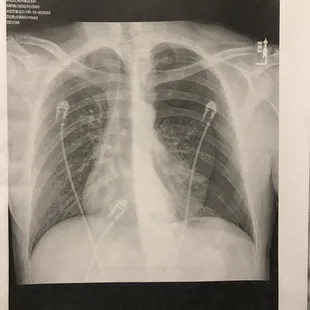

X-ray done in Phoenix showing a left side Pneumothorax

My lung collapsed while I was vacationing in the Outer Banks. I went to this facility after experiencing severe chest pain. Due to the severity of the symptoms, I was seen immediately by their Doctor. My blood pressure at the time was 153/102 (which is Stage 2 Hypertension). Despite noting that I could hear a popping noise when breathing in and out, the Doctor never thought to perform a chest x-ray. A few days later after returning to Phoenix (where I live) I was admitted to the hospital because my lung was 70% collapsed. This facility missed big time as the plane ride home should have killed me. After complaining to the facility about this case, they claimed "the care was appropriate based on presentation and symptoms." The standard of care fell below any acceptable threshold and I would avoid visiting this facility at all costs.